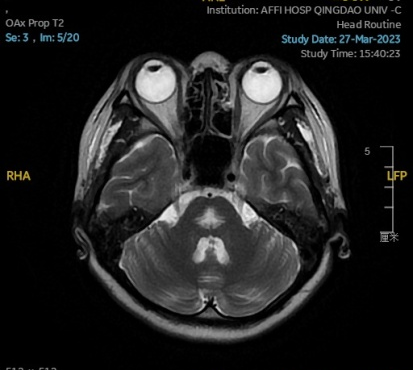

2023.03.27颅脑MR平扫示双侧基底节区及桥脑异常信号,考虑渗透性脱髓鞘综合征,较前范围略减小,请结合临床,见图4。

图4 2023.03.27双侧基底节区及桥脑见对称性片样长T1长T2信号,FLAIR呈高信号,较2023-02-24MR所示范围减小。脑室、脑池、脑沟、脑裂未见明显异常,中线结构居中。